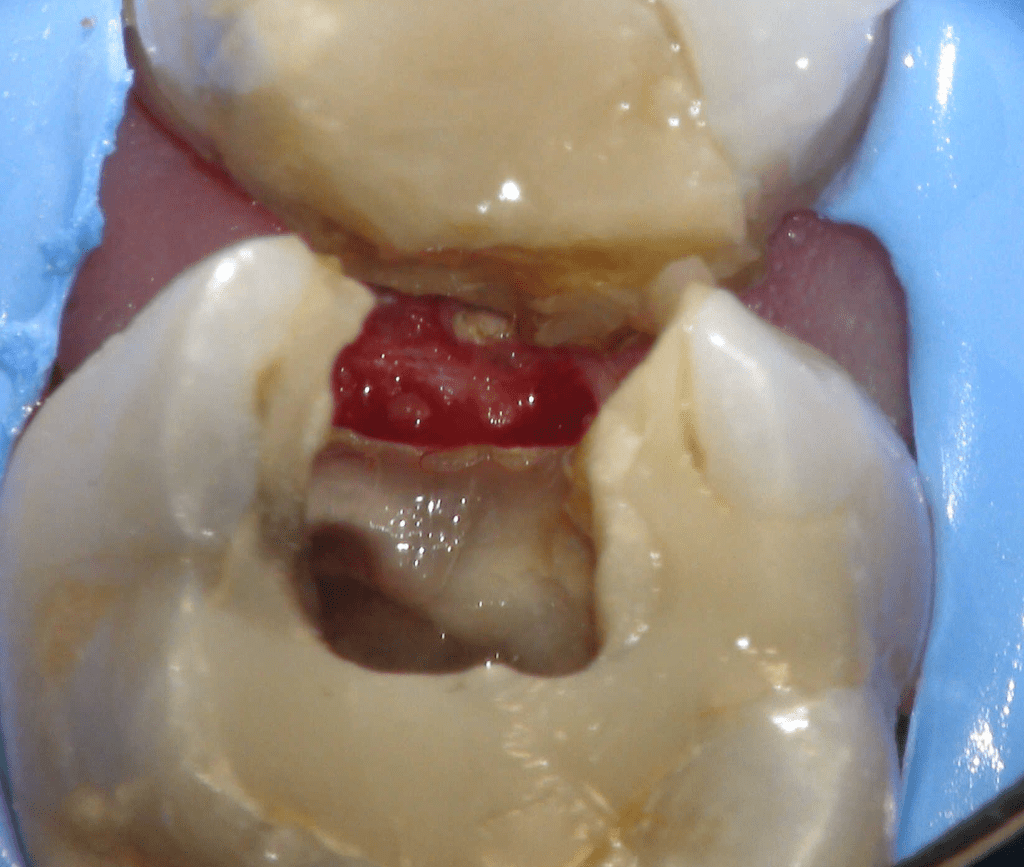

Reconstrucción preendodóntica

Reco pre-endo gingivectomái, pared yuxtaosea

Reco pre-endo, molar inferior

Reco preendo + 4 conductos molar superior

Reco preendo + gingivectomía